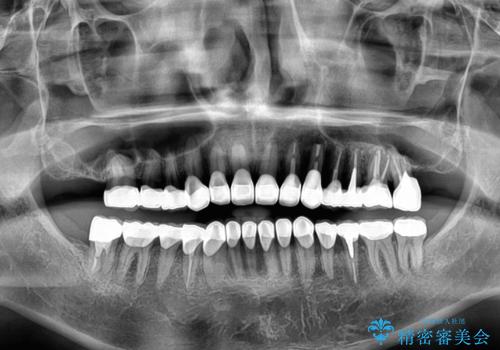

- すぐに欠けてしまう前歯や、むし歯で全顎的に処置された歯を気にして来院された患者様です。

元来むし歯が多く、さらに受け口傾向の咬み合わせを気にしていらっしゃいました。

当初はむし歯処置が必要な歯のみの治療予定でしたが、捻転や咬み合わせを可及的に改善したいとのことで、全顎的にオールセラミッククラウンにて補綴治療を行うこととしました。

反対咬合を補綴治療で改善すると、上唇へ歯が当たる感覚や、発音時の舌感覚が急激に大きく変化するため、違和感になれるまで時間を要することになります。

仮歯で過ごす期間を一定期間も受けることで徐々に変化になれていくようにし、オールセラミッククラウン装着時には違和感なく過ごすことができるようにしています。